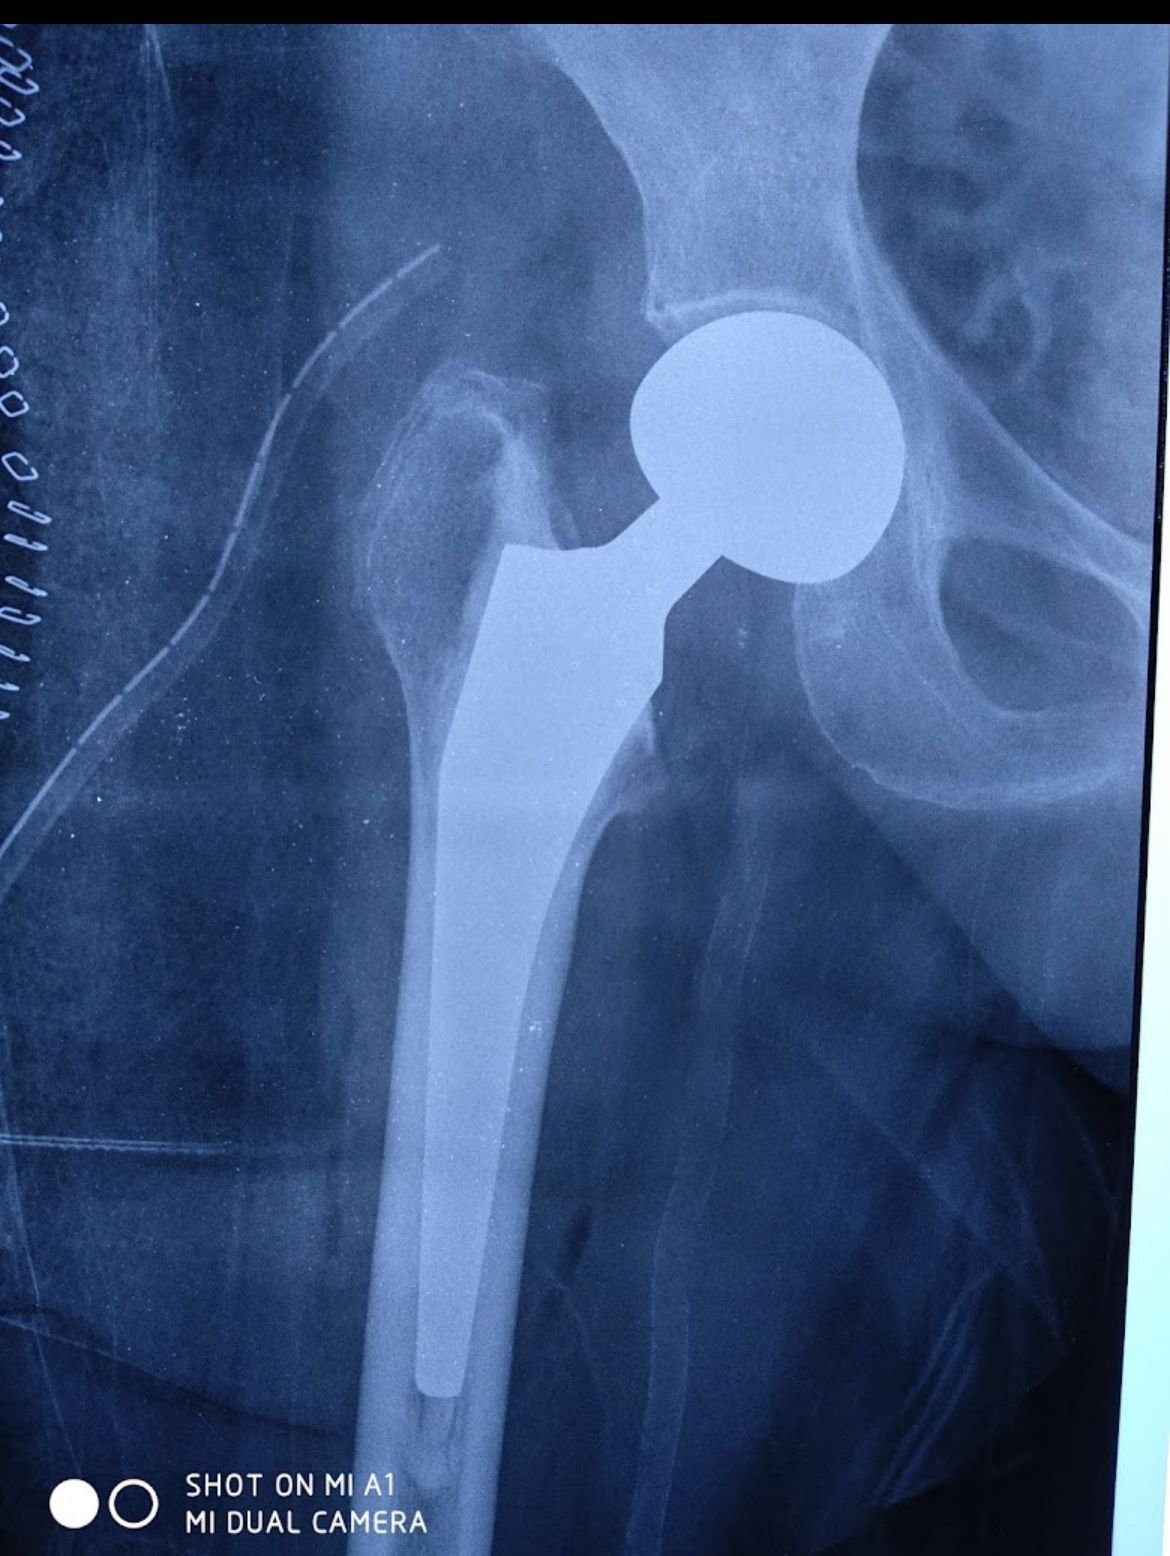

Hip Replacement